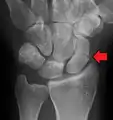

| An X-ray showing a fracture through the waist of the scaphoid | |

A subtle scaphoid fracture

A more obvious scaphoid fracture on a scaphoid view X ray

Radiolucency around a 12 days old scaphoid fracture that was initially barely visible.[13]